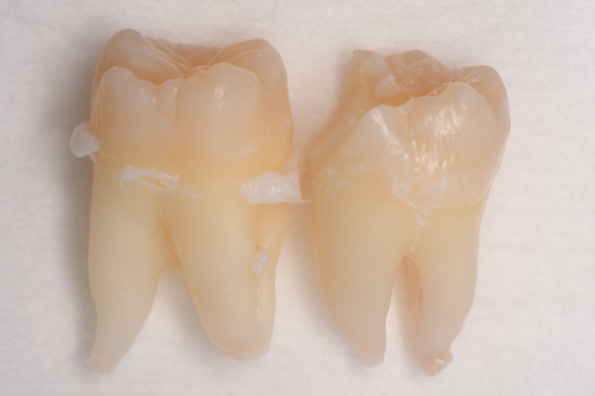

CASE 1

基本情報

| 年齢・性別 | 30代・女性 |

| 主訴 | 左右に分けて親知らずを抜きたい、できれば痛くなく抜きたい |

| 親知らずのはえ方 | 完全に出ていてまっすぐはえている |

| 抜歯期間 | 15分 |

| 抜歯費用 | 約2,000円(保険内) |

| 抜歯内容 |

何度か虫歯になり痛みはないが早めに抜きたい。 完全に頭が出ているため歯ぐきを切ったり骨を削らずに抜歯しました。 根の形も単純なため抜歯自体は5分もかからず上下ともに終わりました。 術後痛みや腫れも出ていません。 抜歯後は感染をしやすいため必ず抗生物質を飲み切ってください。 |